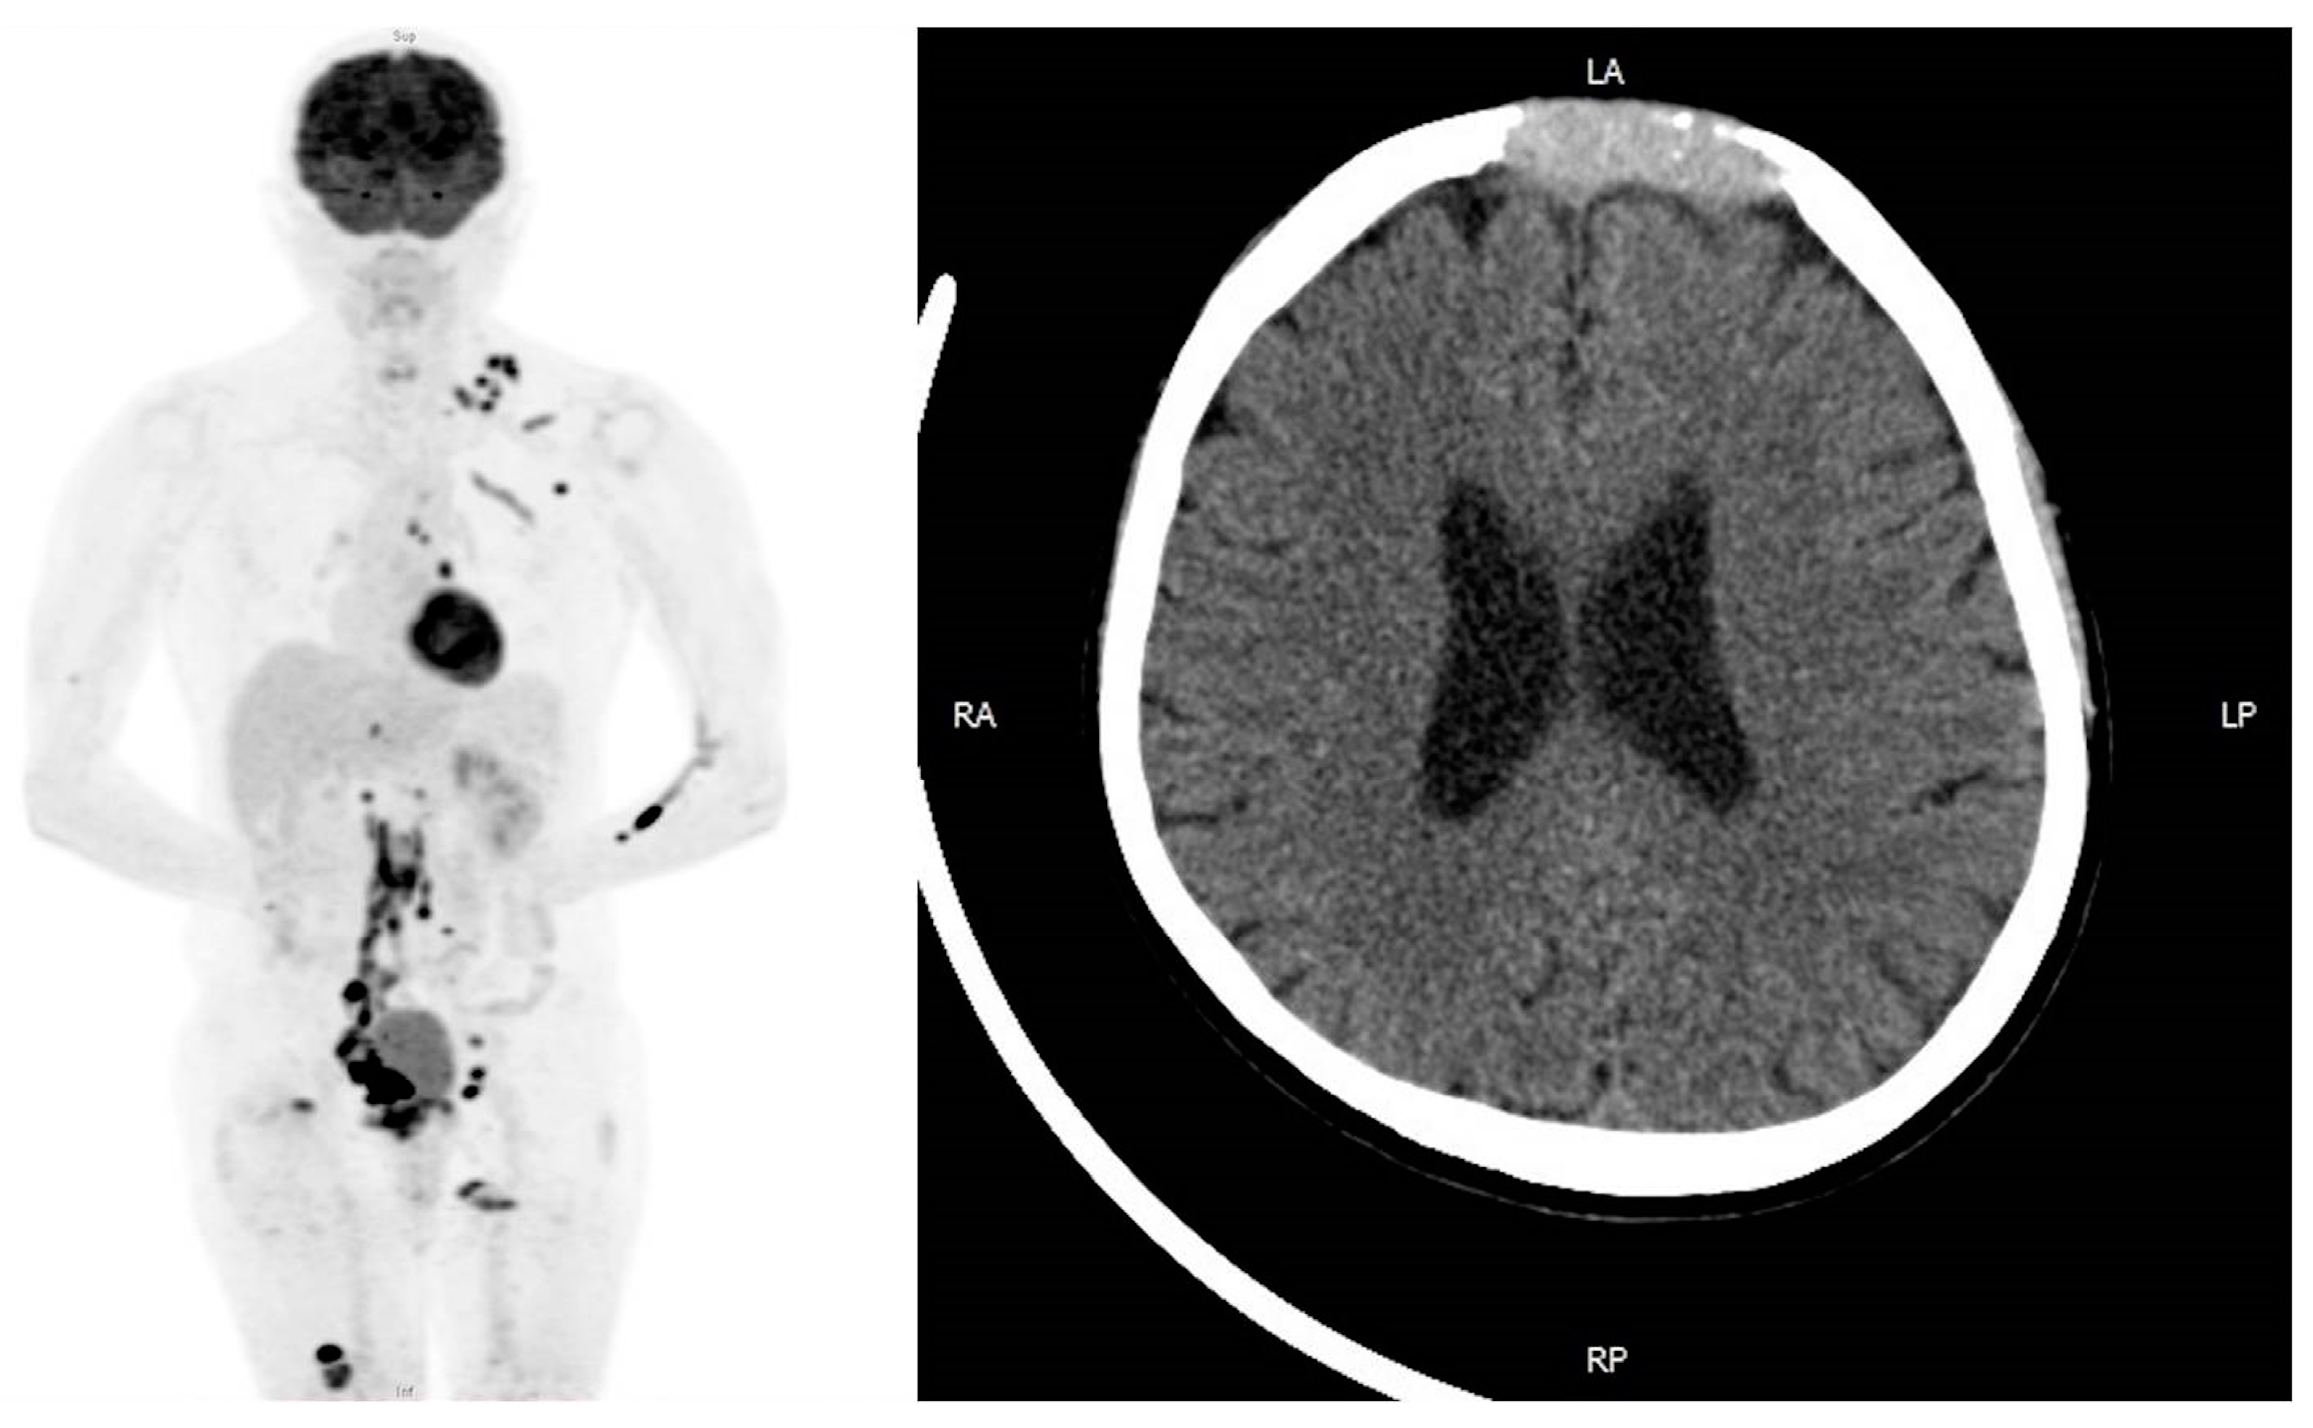

2. Case Presentation